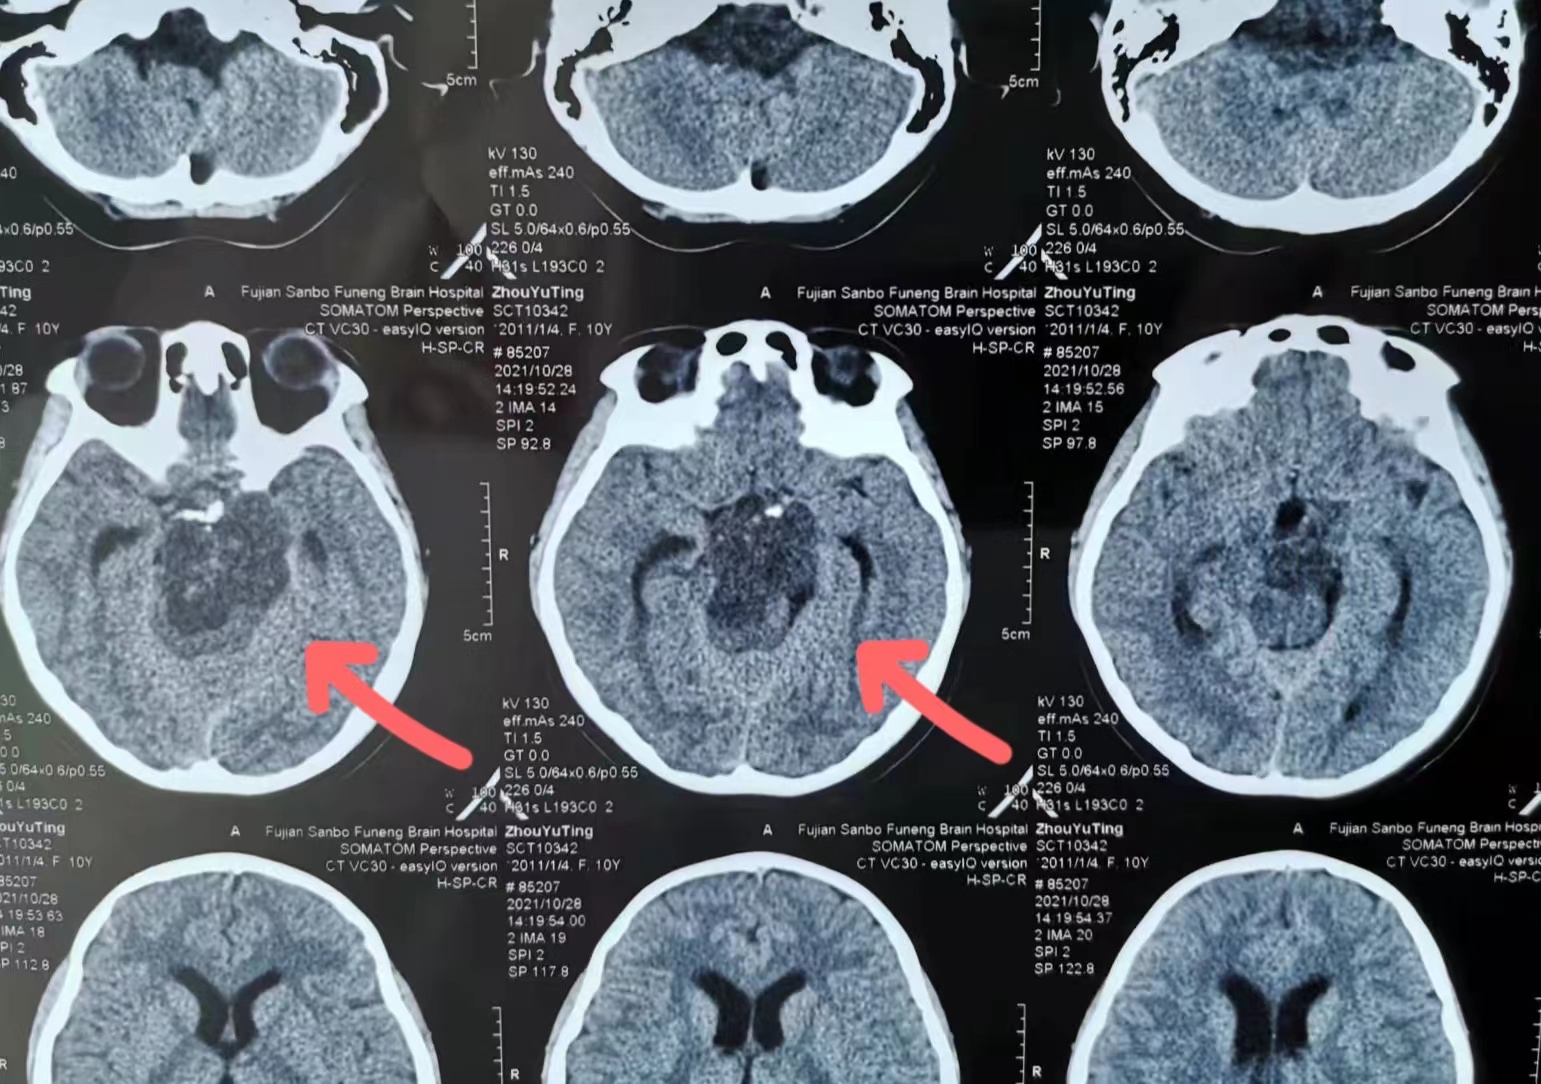

术前影像

在医院神经外科,由林志雄教授、翁超群主任带领的神经外科团队为小玉进行了系统的检查评估,发现孩子的肿瘤位于颅底,属于颅内脊索瘤,与重要的神经、血管及脑和脑干紧密相连;同时与国内多位颅底专家和神经内镜专家反复沟通,均认为通过手术切除肿瘤,难度高、风险大。但为了孩子的未来,专家团队决定放手一搏。

3日上午,小玉被推进手术室,历经6小时“奋战”,我院神经外科专家团队在双镜(脑室镜、显微镜)下切除了位于脑深处的巨大脊索瘤(5.5cm×5.1cm),手术过程顺利。术后,孩子清醒,神经功能没有出现新的损害。